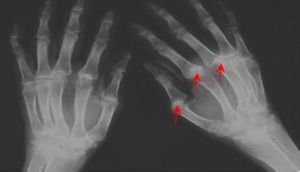

X線檢查早期骨皮質糜爛,可見骨膜的骨新生;長期患者,跟腱、足底部腱膜鈣化,非對稱性骶髂關節炎,以及關節破壞,關節腔狹窄;MRI顯示;在皮質下骨可見炎症性改變,易發生在小關節和骶髂關節。血液學血沉和C-反應蛋白在急性期反應性關節炎可明顯增高,在進入慢性期者則可降至正常。血常規檢查可見白細胞、淋巴細胞計數增高或出現輕度貧血。在部分患者可見尿中白細胞增高或鏡下血尿,很少出現蛋白尿。